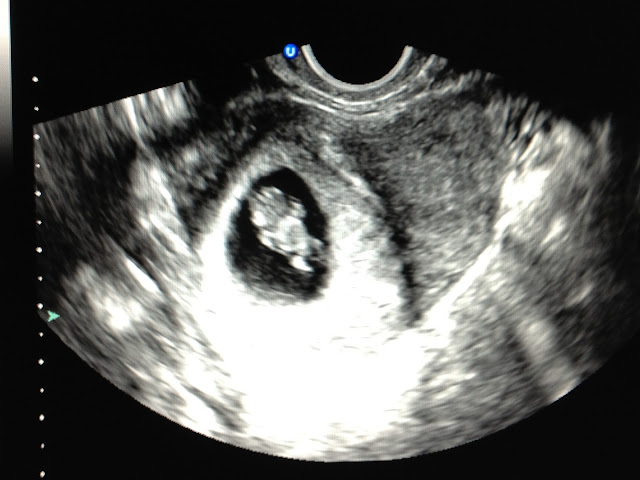

| Baby Brown @ 8 Weeks!! |

Look at how tiny Miss Samantha was!! Barely there and already causing so much excitement in our lives.

| Baby Brown @ 10 Weeks!! |

She was looking pretty good!! And I was feeling worse and worse! Which my loving Dr. would always reassure me was a good sign that Baby was healthy.